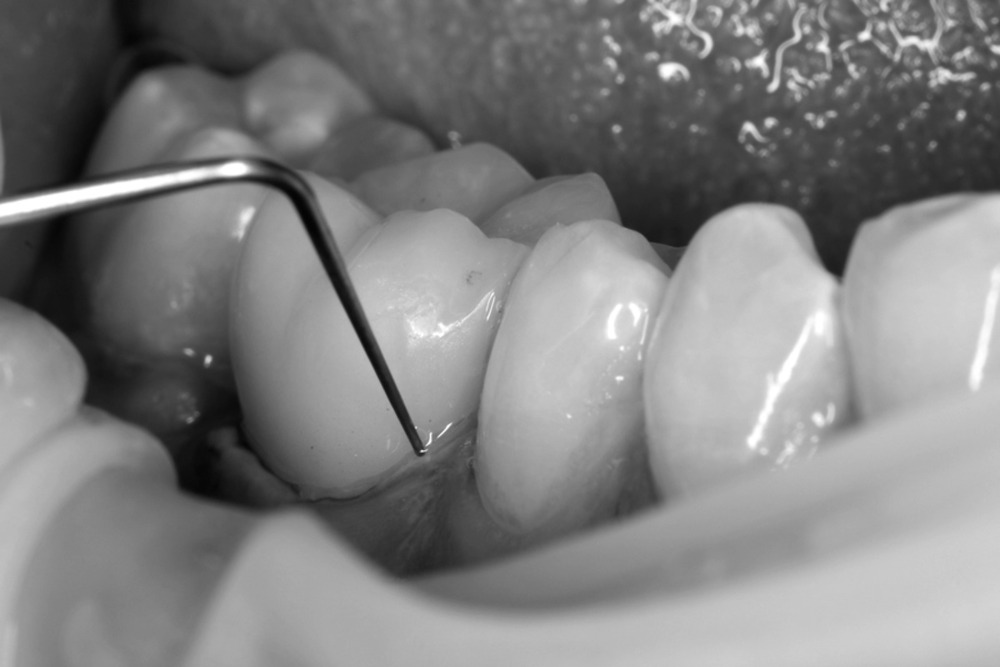

Зубы препарировали в соответствии с традиционными принципами препарирования под безметалловую CAD/CAM коронку [6, 7] (рис. 1).

Коронку припасовывали при помощи артикуляционного спрея в полости рта и полировали до «зеркального блеска» набором полиров, рекомендованных компаниями-производителями. Фиксацию коронок проводили на цемент двойного отверждения Variolink II («Ivoclar Vivadent», Лихтенштейн). После лечения в день фиксации и на контрольных осмотрах получали фото соответствующего зубного ряда и прицельное фото зуба с коронкой и диагностическим зондом (рис. 3).

При оценке краевого прилегания коронки из полевошпатной керамики у 1 пациента из 2-й группы через 12 мес после фиксации была выявлена незначительная маргинальная щель менее 150 мкм, размер которой был проконтролирован специальным диагностическим зондом с толщиной рабочей части 150 мкм (рис. 5).

Через 24 мес после фиксации коронок в 1-й и 2-й группах появились пациенты, у которых коронки получили оценку 2 балла («клинически хорошо») вместо 1 балла («клинически превосходно») по критерию «краевое прилегание». Оценке 2 балла клинически соответствует появление маргинальной щели (<150 мкм), которая определяется специальным зондом. Данный дефект устраняли путем полирования области «цементного шва». В дальнейшем это не повлияло на качество проведенного ортопедического лечения.